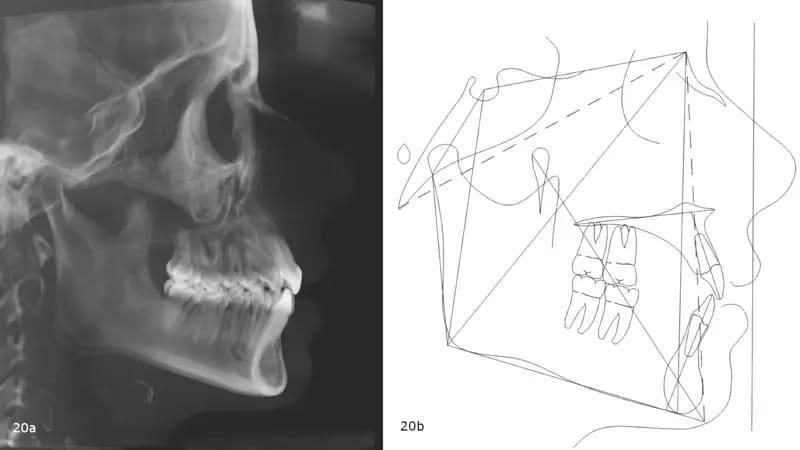

Панорамная рентгенограмма показала предварительное удаление всех третьих моляров, локальную резорбцию корней нескольких зубов, в целом хорошее состояние пародонта и атипичную морфологию мыщелков, свидетельствующую о ремоделировании височно-нижнечелюстного сустава (ВНЧС) или дегенеративных изменениях (фото 19). Цефалометрическая рентгенограмма и трассировка выявили мезобрахиально-лицевой тип скелета и тенденцию к формированию скелета II класса (фото 20).

Фото 20a-b: Дооперационная цефалометрическая рентгенография перед лечением (а) и трассировка (b).